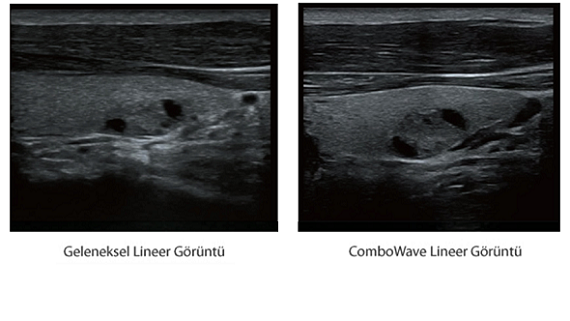

X-Insight, daha geli?mi? g?rĂŒntĂŒler elde etmek i?in kapsaml? bir ??zĂŒmdĂŒr.

Mindrayâin yeni ??zĂŒmĂŒ, geli?en en yeni ultrason teknolojileri ile birlikte, mĂŒ?terilerin g?rĂŒ?lerini klinik gerekliliklerle tam anlam?yla birle?tiren bir ??zĂŒmdĂŒr. Taptaze bir ruhla, gelece?e odaklanarak ve s?n?rs?zl???n pe?inde ko?arak, artan ?l?eklenebilirlikte sĂŒrekli olarak geli?en bir ??zĂŒmdĂŒr.

MĂŒ?teri gereksinimlerine y?nelik g?rĂŒ?ler temelinde, X-Insight'l? DC-60 Exp, eXpress Clarity, eXceptional Intelligence ve eXceeding Experience ile gĂŒ?lendirilerek, hassas g?rĂŒntĂŒlemeyle yĂŒksek verimlilik sa?layacak ?ekilde tasarlanm??t?r.